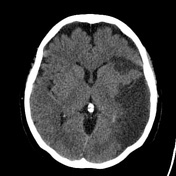

운동 기능이나 감각 기능의 focal impairment(eg, hemiparesis)로 나타나는 주요 neurologic deficit이 새롭게 나타나거나 seizure가 나타나는 경우 cerebrovascular circulation과 관련된 문제가 그 원인일 수 있다. 내과계 중환자에서 CT 촬영의 유용성을 평가한 연구에서 ischemic stroke(허혈성 뇌졸중)와 intracranial bleeding(두 개 내 출혈)이 새롭게 발생한 neurologic defecit(신경학적 결손)이나 seizure의 가장 흔한 원인으로 확인되었다.

전반적으로 새로 발병한 stroke의 빈도는 내과계 중환자에서 1 ~ 4%이고, 외과계 중환자에서 수술 전후로 stroke가 0.3 ~ 3.5%에서 발생하였다. 심장 수술이나 혈관 수술을 받은 환자, 그리고 cerebrovascular disease(뇌혈관 질환)을 갖고 있는 환자가 수술을 받는 경우에는 수술 전후 stroke가 발생할 위험이 증가할 것으로 예상할 수 있다. Primary neurologic disorder나 primary neurosurgical disorder로 입원한 환자에서 focal neurologic deficit이 새로 발생하거나 악화되는 빈도는 다양하다. 예를 들어, aneurysmal subarachnoid hemorrhage(동맥류 지주막하 출혈) 환자의 30%에서 delayed ischemic neurologic deficit이 나타났다. Stroke로 입원한 환자는 종종 stroke이 진행되거나, 뇌출혈 혹은 interventional therapy로 open 된 혈관의 reocclusion으로 인해 새로운 증상이 나타나거나 이전 증상이 악화될 수 있다. Elective intracranial surgery를 받은 환자에서 수술 후 출혈이나 감염 합병증은 새롭게 나타나는 focal deficit의 원인일 수 있다. 외상 환자에서는 인지되지 못한 cerebrovascular circulation에 대한 손상이 새로운 deficit을 유발할 수 있다.